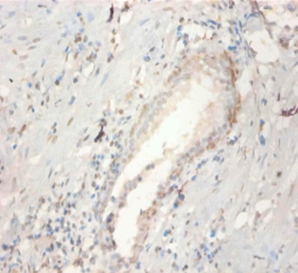

Immunohistochemical analysis of paraffin-embeded human prostate using #42458 at dilution of 1:100.